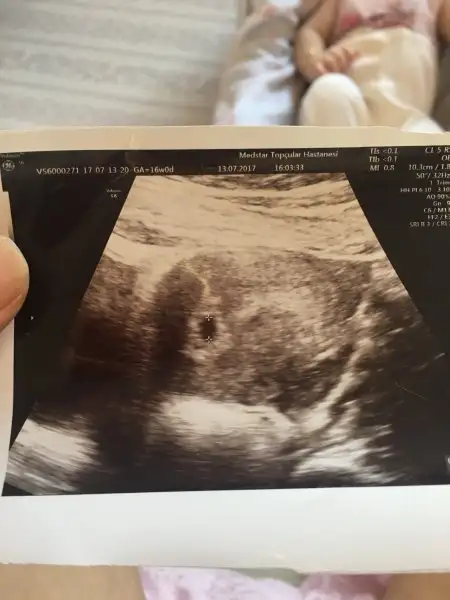

Büyük kese kızımın 6. Haftadaki ultrasonu diğeri simdiki gebeliğimin